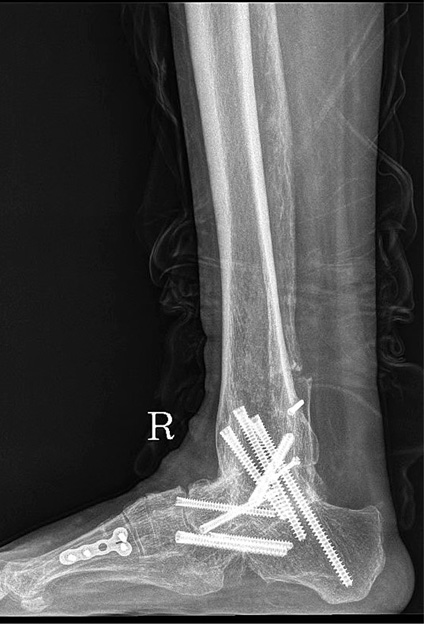

为最大限度提升术后效果,梁晓军为患者进行了全面完善的术前检查和准备。2月28日,肖某玲迎来了手术日。手术打开已经生长在一起的骨头,将原来的内固定取出,重新松解周围软组织、定位踝关节开放截骨线,最后将人工假体成功植入。“融合术后原来的两块骨头就变成一块了,要重新找到关节面,精确打开,再松解周围组织,手术要求非常高,好在手术顺利完成了。”梁晓军说,术后,肖某玲的踝关节就可以重新活动了。(卫晓康)